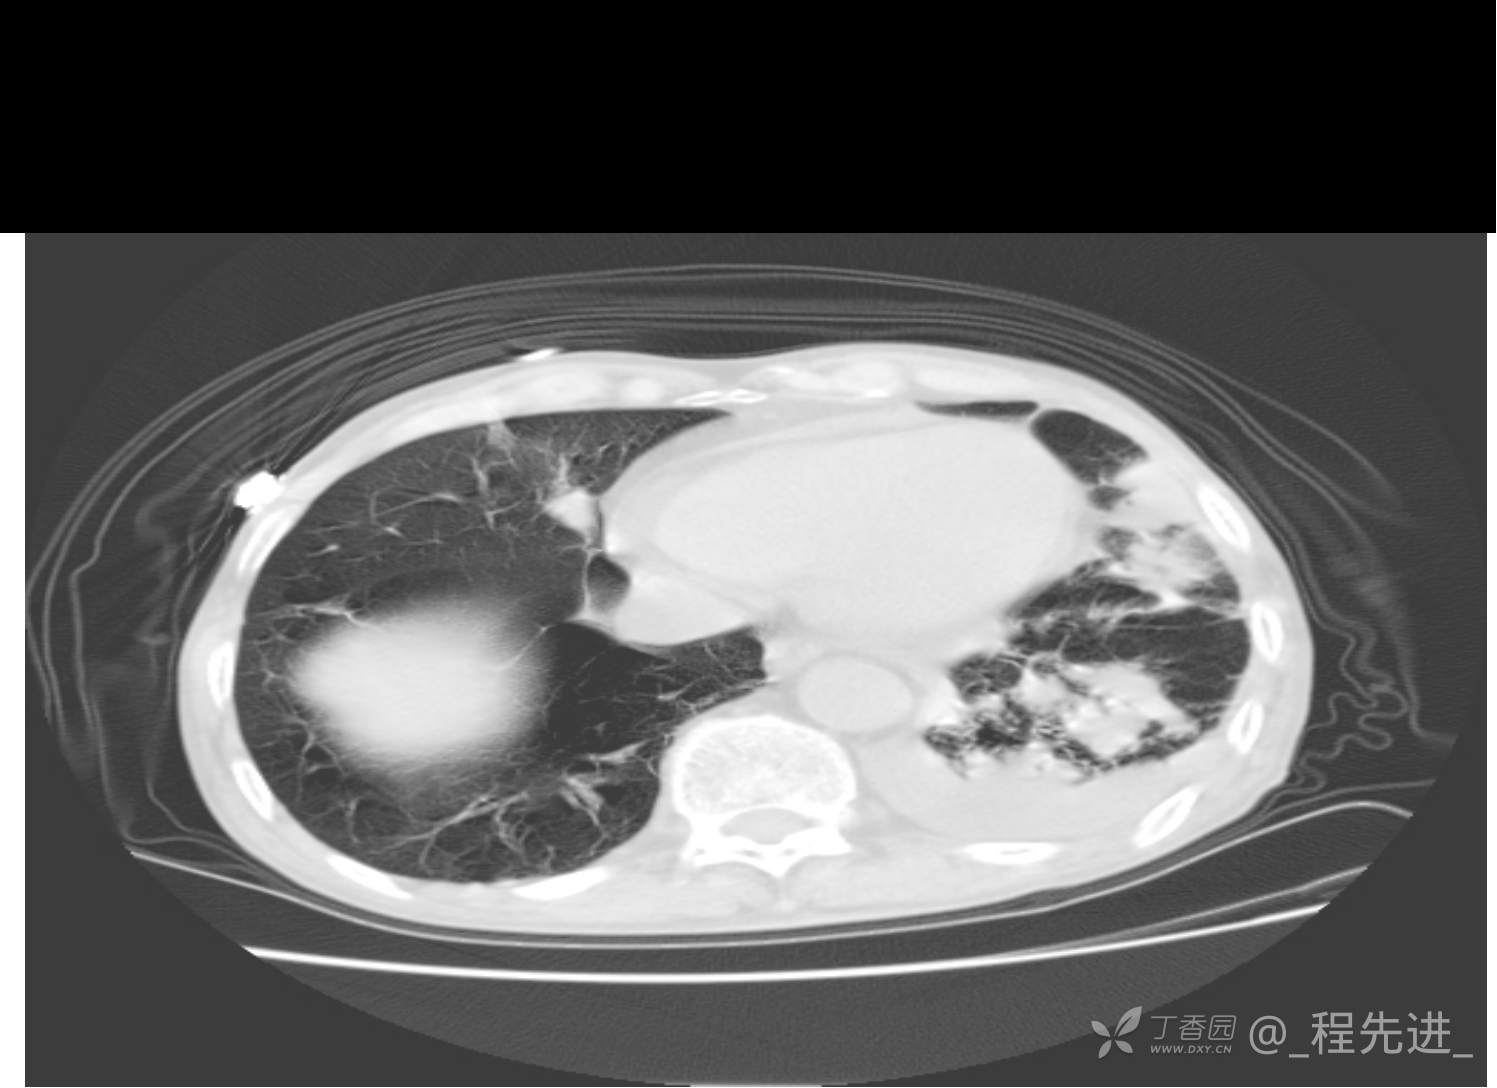

患者性别:男

患者年龄:81岁

简要病史:反复咳嗽、咳痰20余年,加重1周。两肺呼吸音低,可闻及散在干湿啰音。